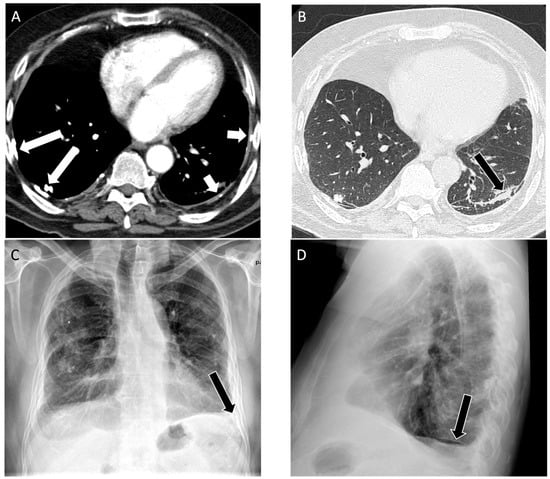

Figure 3.

An 83-year-old male with 75 pack year smoking history and asbestos exposure from construction work, diagnosed with asbestosis. (A) Axial computed tomography image demonstrates subpleural reticulation (black arrows) and mild traction bronchiectasis (white circle) of right lung in keeping with mild asbestosis; (B) mediastinal windows demonstrate a calcified pleural plaque along the right diaphragm (white arrow); (C) posteroanterior and (D) lateral chest radiograph demonstrate mild reticular markings in the basal lung consistent with mild fibrosis, best appreciated in the left lateral costophrenic angle (white circle).